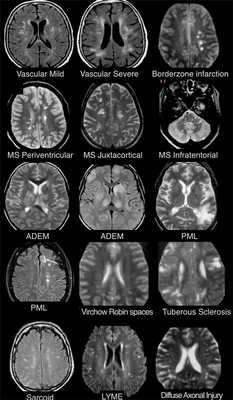

На изображениях определяются множественные точечные и «пятнистые» очаги (некоторые из них будут рассмотрены более детально).

Рассеянный склероз — хроническое аутоиммунное заболевание, при котором поражается миелиновая оболочка нервных волокон головного и спинного мозга, характеризующееся многоочаговостью поражения белого вещества центральной нервной системы, ремиттирующе-прогредиентным течением, вариабельностью неврологических симптомов и преимущественным поражением лиц молодого возраста (подробнее с диагностическими критериями указанного заболевания Вы можете ознакомится в статье «Современные критерии диагностики рассеянного склероза», опубликованной на нашем сайте).

- Главное отличие инфарктов (инсультов) этого типа — это предрасположенность к локализации очагов только в одном полушарии на границе крупных бассейнов кровоснабжения. На МР-томограмме представлен инфаркт в бассейне глубоких ветвей.

- Основное отличие: появление мультифокальных участков в белом веществе и в области базальных ганглиев через 10-14 дней после перенесенной инфекции или вакцинации. Как при рассеянном склерозе, при ОДЭМ может поражаться спинной мозг, дугообразные волокна и мозолистое тело; в некоторых случаях очаги могут накапливать контраст. Отличием от РС считается тот момент, что они имеют большой размер и возникают преимущественно у молодых пациентов. Заболевание отличается монофазным течением

- Распределение очаговых изменений при саркоидозе крайне напоминает таковое при рассеянном склерозе.

- Демиелинизирующее заболевание, обусловленное вирусом Джона Каннигема у пациентов с иммунодефицитом. Ключевым признаком являются поражения белого вещества в области дугообразных волокон, не усиливающиеся при контрастировании, оказывающие объемное воздействие (в отличие от поражений, обусловленных ВИЧ или цитомегаловирусом). Патологические участки при ПМЛ могут быть односторонними, но чаще они возникают с обеих сторон и являются асимметричными.

- Ключевой признак: гиперинтенсивный сигнал на Т2 ВИ и гипоинтенсивный на FLAIR

- Для зон сосудистого характера типична глубокая локализация в белом веществе, отсутствие вовлечения мозолистого тела, а также юкставентрикулярных и юкстакортикальных участков.